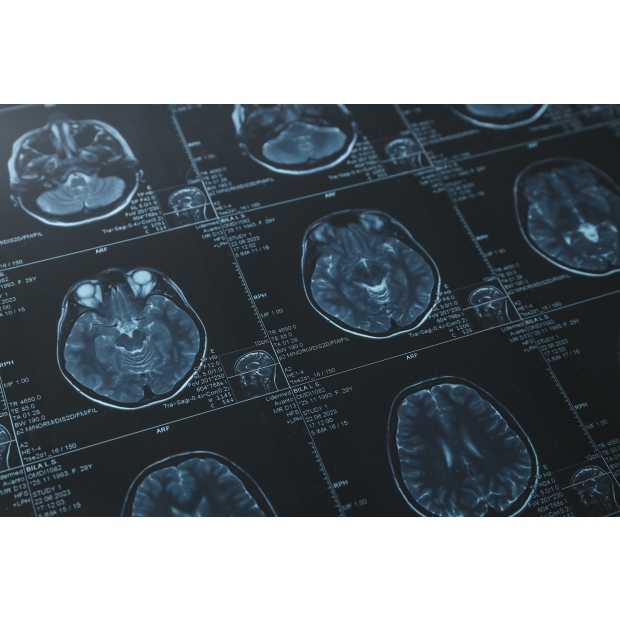

DeepBT is a software system intended to assist trained medical professionals during their clinical workflows of radiation therapy treatment planning. DeepBT is applicable only to adult patients with known imaging diagnosis of acoustic neuroma, meningioma, and brain metastasis. The product can take either single parametric magnetic resonance (MR) images (T1W+C) or bi-parametric MR images (T1W+C and T2W) as inputs, then automatically interpret MR images, and provide the lesion contours without requiring manual preprocessing or annotation.

• Automatic classification of various brain tumors in MRI

• Automatic segmentation of various brain tumors in MRI

Using our proprietary AI technology, we perform automatic segmentation of various types of brain tumors (such as acoustic neuroma, meningioma, and brain metastasis) on preoperative MRI scans, providing objective and accurate volumetric analysis of the tumors.